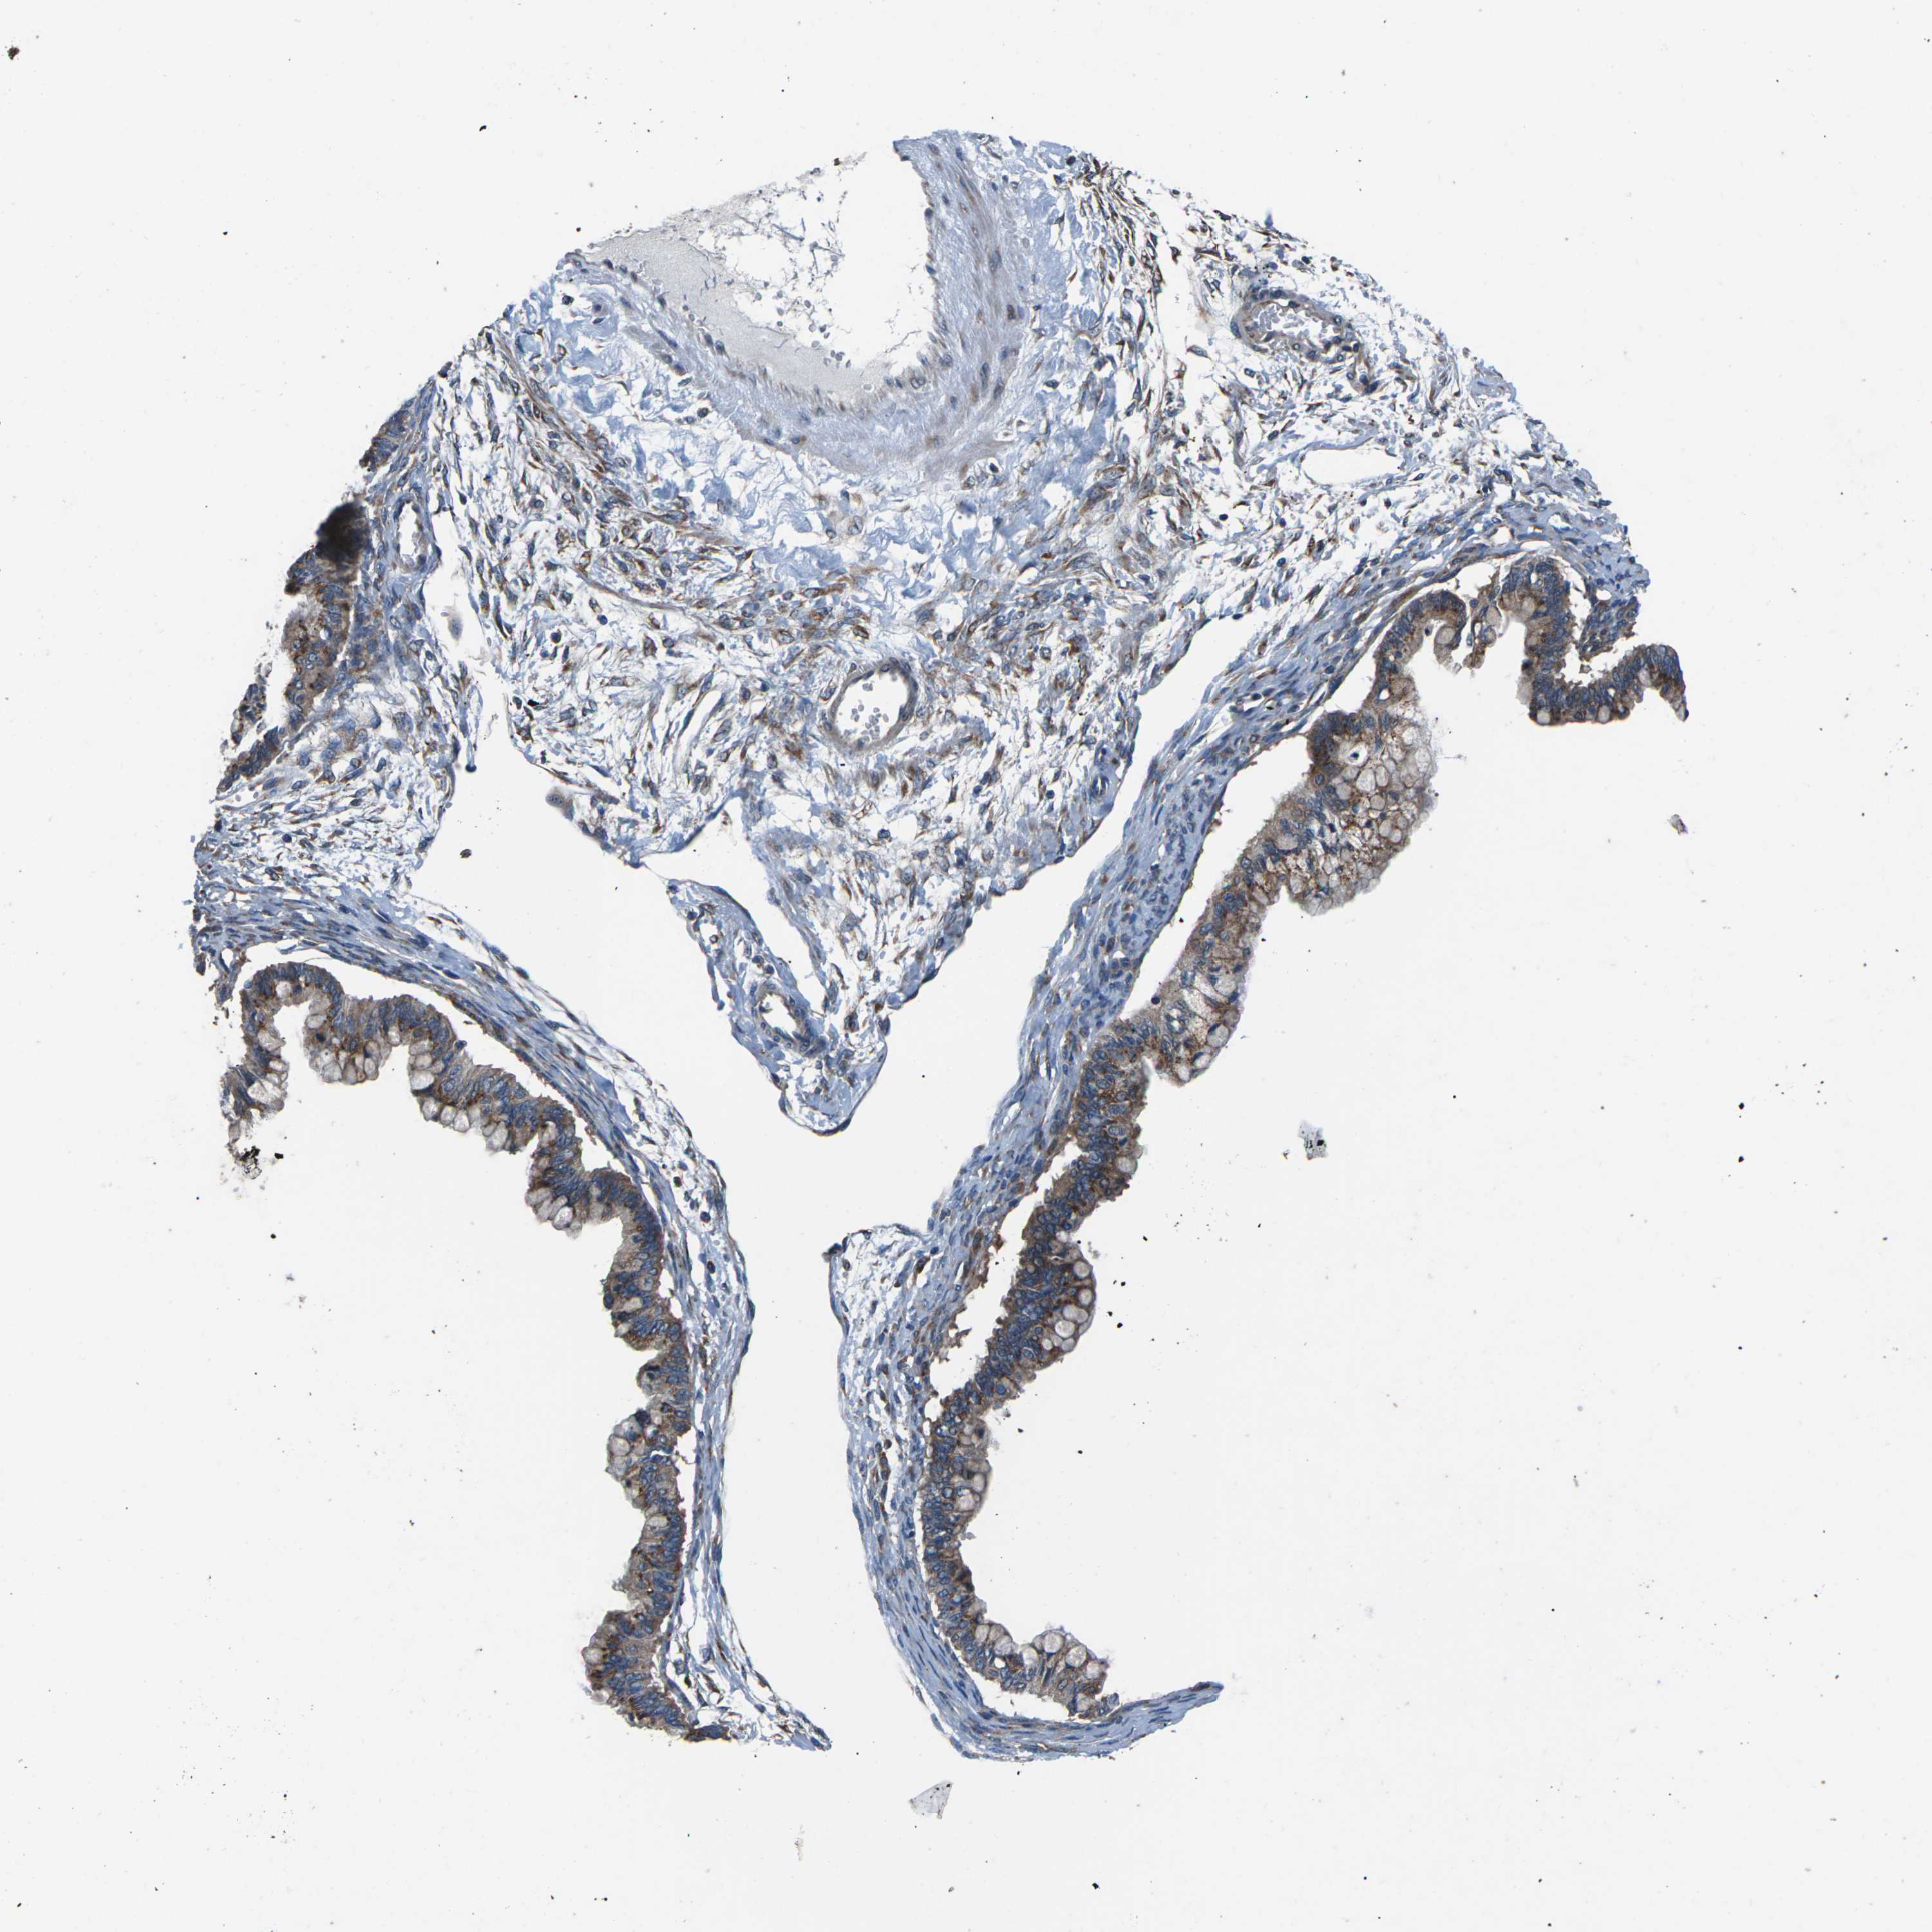

OVARIAN CANCER - Protein expressioni

A mouse-over function shows sample information and annotation data. Click on an image to view it in a full screen mode. Samples can be filtered based on level of antibody staining by selecting one or several of the following categories: high, medium, low and not detected. The assay and annotation is described here.

Note that samples used for immunohistochemistry by the Human Protein Atlas do not correspond to samples in the TCGA dataset.

Antibody stainingi

Antibody staining in the annotated cell types in the current human tissue is reported as not detected, low, medium, or high, based on conventional immunohistochemistry profiling in selected tissues. This score is based on the combination of the staining intensity and fraction of stained cells.

Each image is clickable and will lead to virtual microscopy that enables deeper exploration of all samples and also displays staining intensity scores, fraction scores and subcellular localization as well as patient and tissue information for each sample.

Antibody CAB014883

Staining

High

Medium

Low

Not detected

Intensity

Strong

Moderate

Weak

Negative

Quantity

>75%

75%-25%

<25%

None

Location

Nuclear

Cytoplasmic/membranous

Cytoplasmic/membranous,nuclear

Cystadenocarcinoma, serous, NOS

Carcinoma, endometroid

Cystadenocarcinoma, mucinous, NOS

Carcinoma, NOS